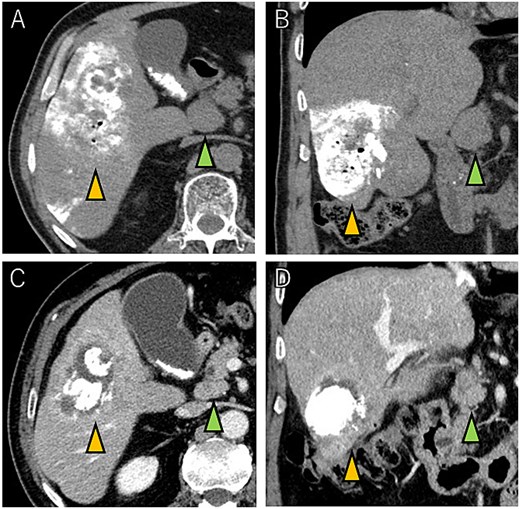

A 72-year-old man presented with abdominal pain. Computed tomography (CT) revealed a liver tumor in segment six/five, abutting the transverse colon without invading. Enlarged lymph nodes in regions 12b and 16b1 were noted, but there were no lung metastases or ascites. Magnetic resonance imaging revealed multiple nodular lesions in liver S6/5 with low signal intensity on T1-weighted images, and mosaic-like high signal intensity on T2-weighted images (Fig. 1). Based on these findings, the diagnosis of HCC was made, staged as cT2N1M1 Stage IVB. The patient underwent transarterial chemoembolization (TACE) followed by ATZ + BV therapy, resulting in tumor and lymph nodes reduction (Fig. 2).

Magnetic resonance imaging showing multiple nodular lesions in liver S6/5 with low signal intensity on T1-weighted images (A), and mosaic-like high signal intensity on T2-weighted images (B).